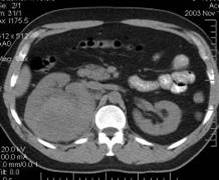

CHISTELE RENALE SIMPLE sunt situate în corticala si pot proemina fie spre exteriorul conturului renal, fie spre medulara. Sunt rotunde, cu contur propriu, bine delimitate, de dimensiuni variabile. La urografie, sistemul pielo-calicial este amprentat si dislocat de chiste. Diagnosticul diferential cu cancerul renal sau alte tumori benigne renale este posibil prin arteriografie renala, ecografie (imagini rotunde, transsonice, cu perete propriu) sau prin CT.

POLICHISTOZA RENALA Întreaga masa renala este înlocuita progresiv de numeroase formatiuni chistice. Boala se depisteaza la maturitate (40-50 ani), în faza de insuficienta renala si hipertensiune arteriala severa. Urografic, rinichii sunt mari, cu contur neregulat, boselat, iar sistemul pielo-calicial este complet distorsionat, cu secretie întârziata, simetric, bilateral. Arteriografic, arterele intraparenchimatoase sunt gracile si distorsionate, circulatia este saraca, în schimb arterele renale sunt normale pâna la hil. Aspectele ecografice si CT sunt de asemenea, caracteristice (examenul CT depisteaza mai ales hemoragia intrachistica).